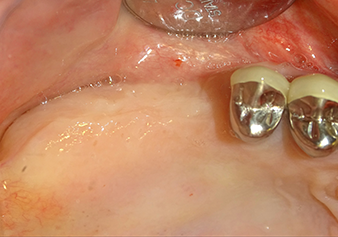

A 49-year-old female patient, a non-smoker and with nothing remarkable in her general medical history, was referred to our oral surgery practice for surgical extraction of tooth 16 and subsequent implantation. After the extraction, the patient experienced mild sinusitis trouble with the resultthat we initially waited six months before carrying out the measure. The residual bone height at the planned implant position measured 3-4 mm (Fig. 1 and 2).

Following atraumatic preparation of the mucoperiosteal flap, the implant position was marked with the I1 instrument and the site prepared – until initial resistance was felt. Piezosurgical instruments were used in an up and down movement without any pressure being exerted. The piezoelectric vibration produced the desired and efficient cavitation.

The I2A instrument (diameter 2.0 mm) was then used to perforate the sinus floor intermittently and on the smallest scale possible. This special piezosurgical method ensures that the Schneiderian membrane is not damaged. When the Z25P was used, the membrane was already lifted slightly by the coolant supplied via the instrument tip (Fig. 3). The coolant quantity was just 50% in order to avoid high pressure in the implant bed.